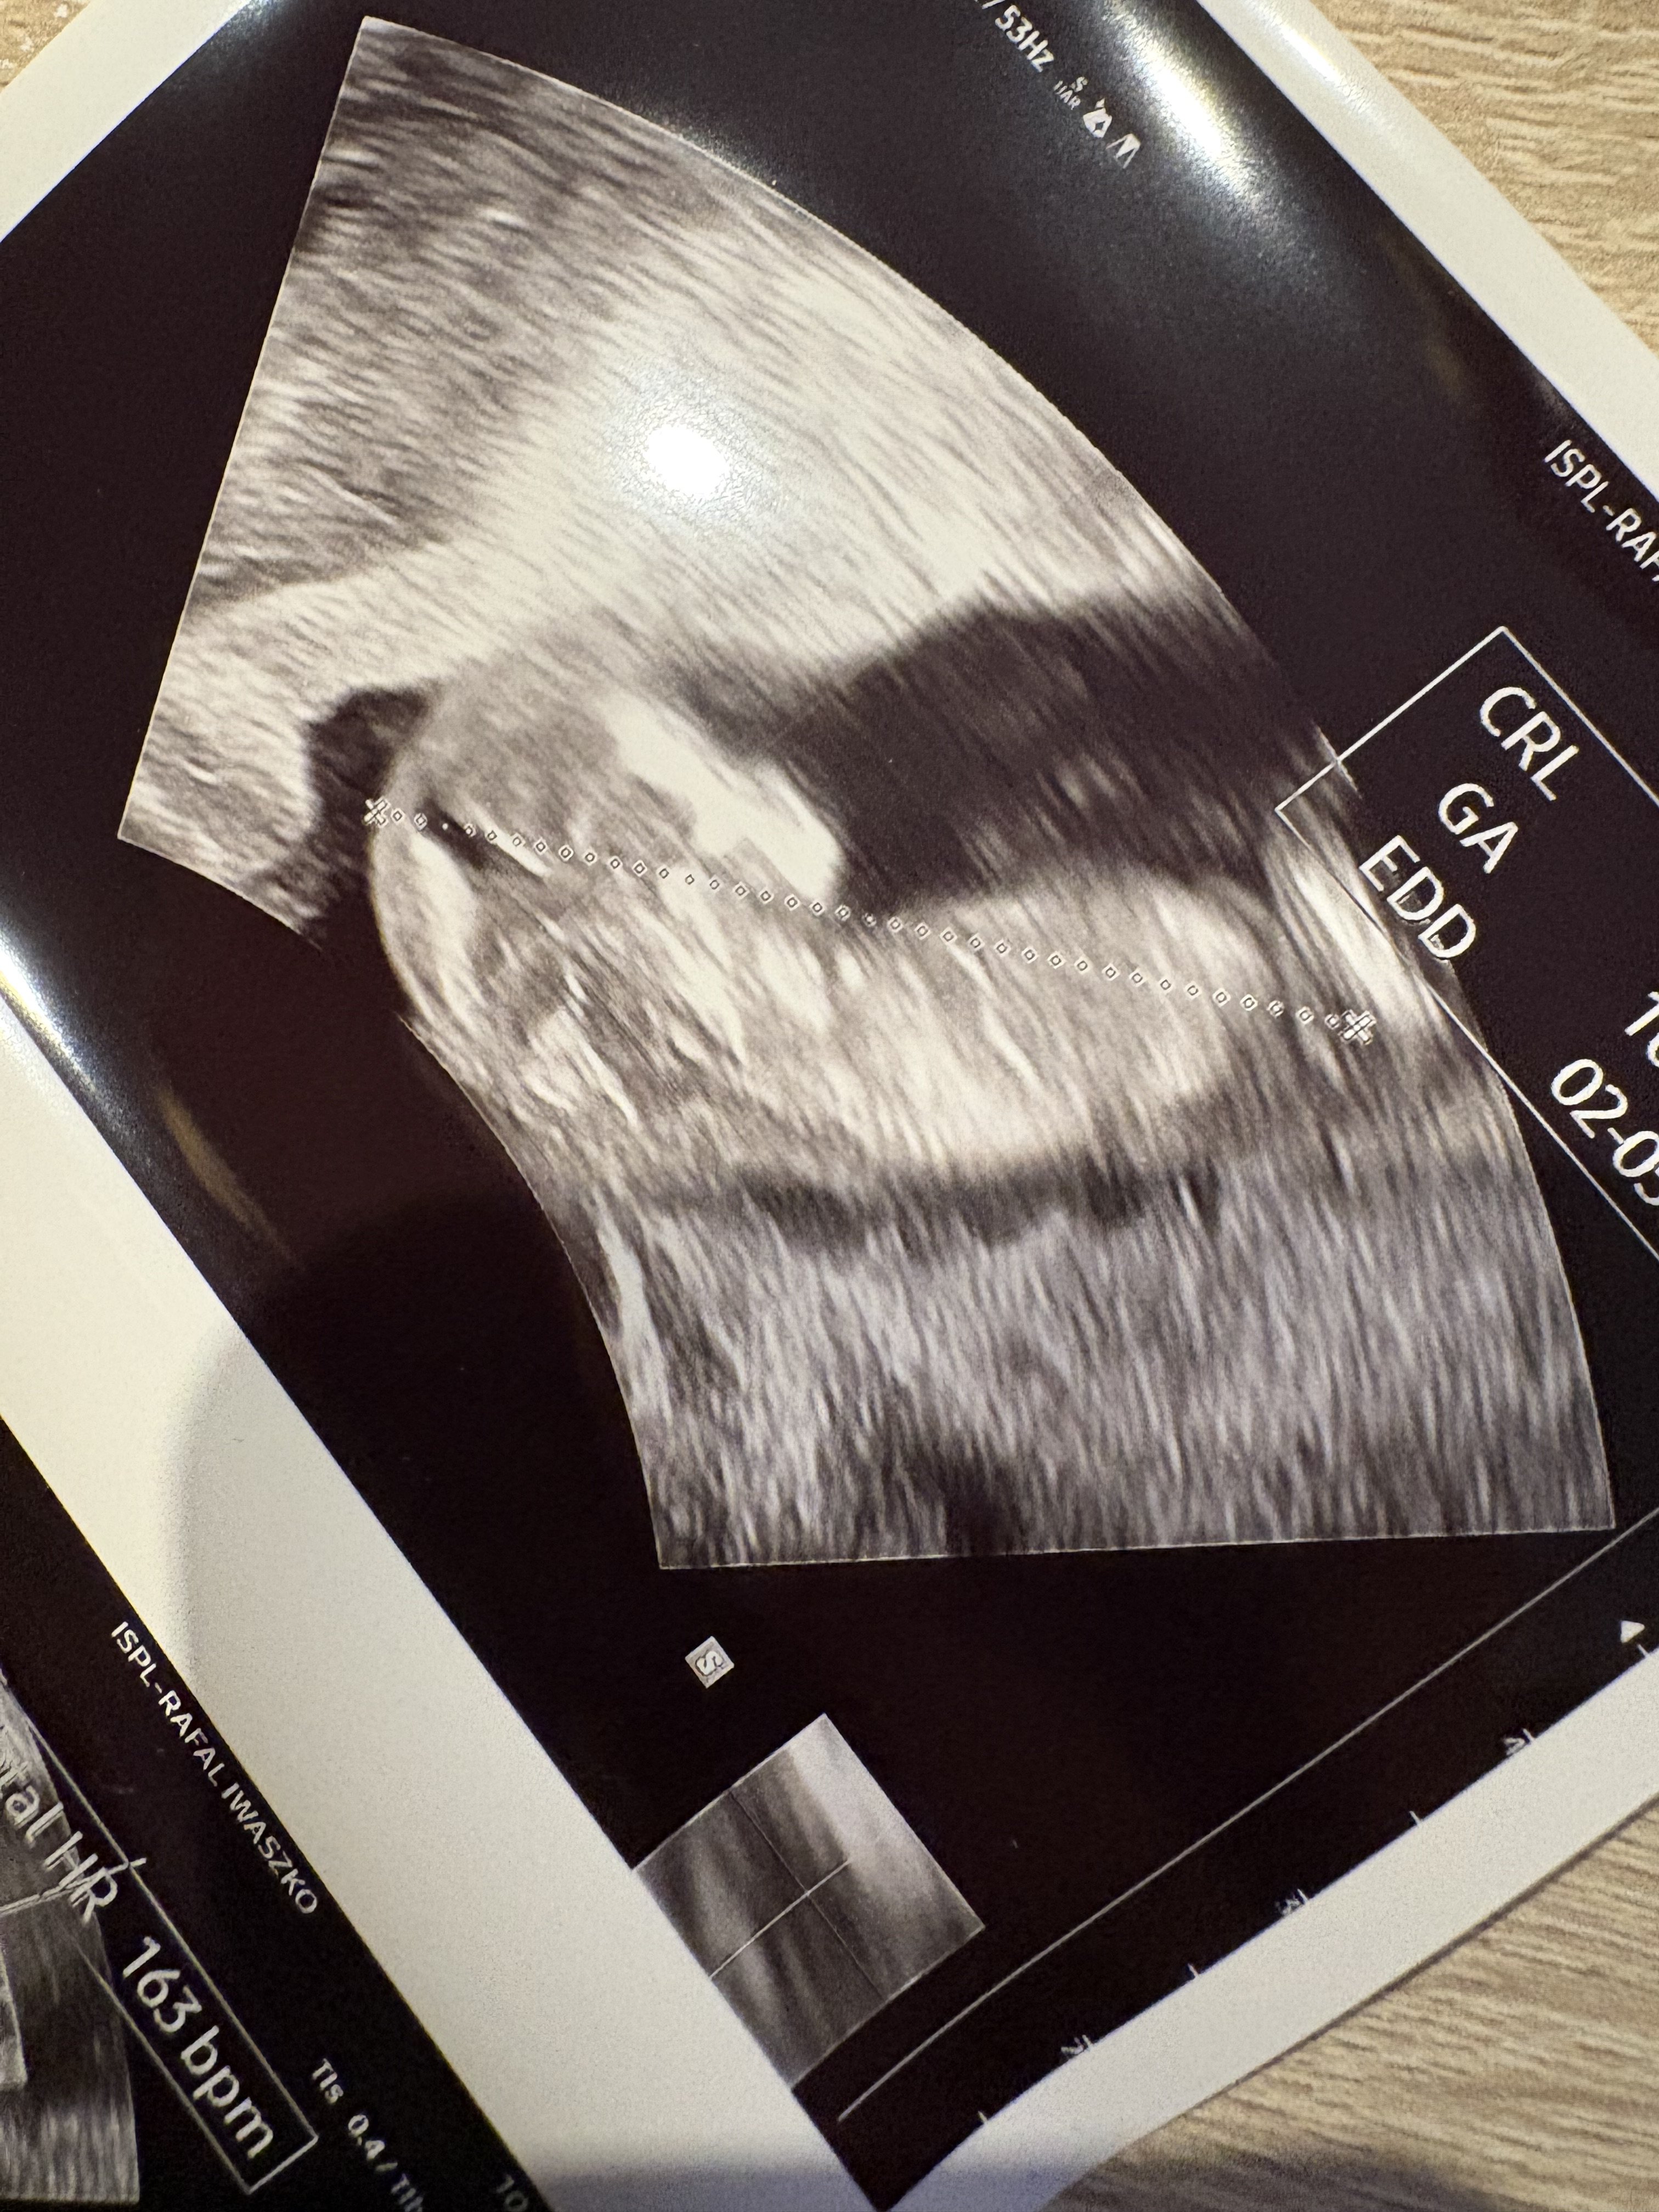

Jestem dziś już po wizycie, 10+6 z USG i wszystko się idealnie zgadza.

Mały człowiek ma 3,87 i był bardzo ruchliwy,ciężko było zrobić fotkę